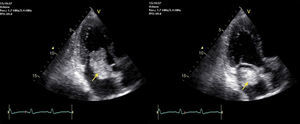

An electromyogram revealed mononeuritis of left posterior tibial nerve with no evidence of myopathy. To rule out arteriographic abnormalities, contrast-enhanced computed tomographic angiography of thorax and abdomen was scheduled. The patient received glucocorticoids (60mg of methylprednisolone in 2 doses) to prevent a probable allergic reaction to the contrast material, which resulted in a notable improvement in his symptoms. The imaging study revealed an intracavitary filling defect at the level of left atrium. This finding led to the performance of transthoracic echocardiography, which disclosed the presence of a large pedunculated tumor in left atrium that was attached to the atrial septum at the level of the fossa ovalis, which prolapsed toward the valve in diastole and was associated with mild mitral regurgitation (Fig. 1).